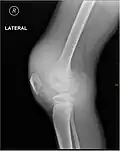

Lipohémarthrose (présence de sang et de graisse dans l'épanchement hémorragique) est une fracture articulaire du plateau tibial interne. La flèche indique un niveau de liquide entre le composant gras supérieur et le composant sanguin inférieur.

L'hémarthrose est un épanchement de sang dans une cavité articulaire consécutif d'une lésion ligamentaire, d'une fracture osseuse ou encore d'une atteinte du cartilage osseux[1]. Cette physiopathologie est caractéristique des personnes atteintes d'hémophilie sévère et dans une moindre mesure chez les formes modérées, car chez les hémophiles, l’absence ou l’altération d’un des facteurs de la coagulation (VIII ou IX selon le type d’hémophilie) perturbe le processus de la coagulation, au point qu’un traumatisme minime peut provoquer un saignement prolongé[2]